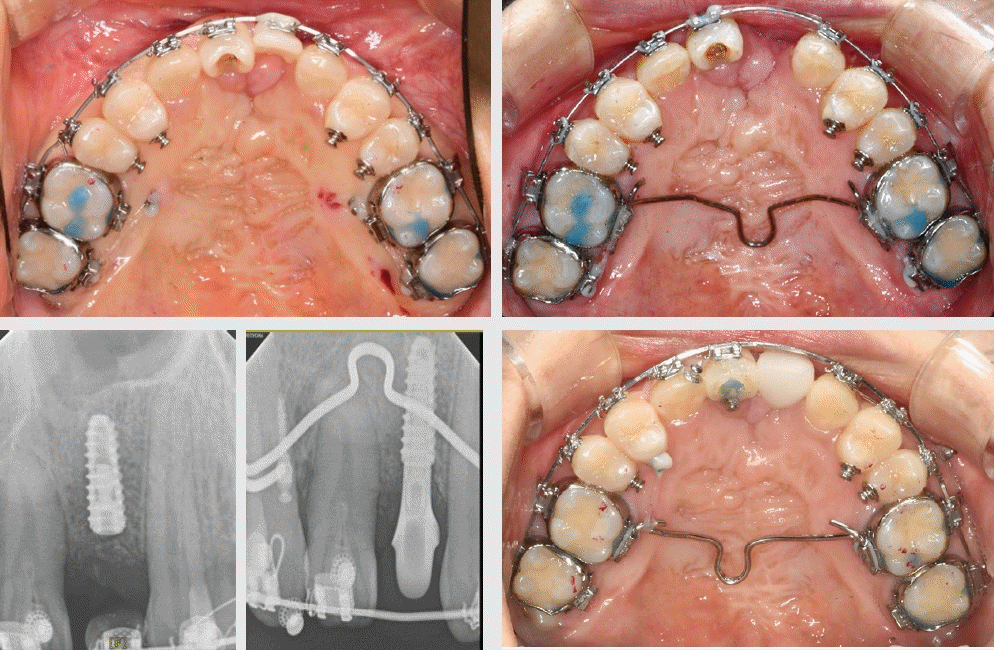

Figure 8.

Upper row: Initial intraoral frontal and maxillary occlusal views.

Lower row: Panoramic radiograph, axial and sagittal views

Figure 9.

Upper row: Transverse discrepancy at Maxillary first and second molars

Lower row: TPA appliance and segmental lingual wire

19세 여성이 치아배열을 바르게 하고 싶다는 주소로 내원하였다. 3세 경 수술 이력과, 10~11세에 양측 장골이식을 받았다고 하였다. 측모의 개선을 위하여 악교정 수술 대안을 설명하였으나, 발치나 더 이상의 큰 수술은 받고 싶지 않다는 의견과 함께, 교정적인 치료의 한계를 수용하기로 하였다.상순에서 구순열 수술을 확인하였고, 구개열의 수술도 관찰되었다. 장골 이식 이력은 진단서로 확인되었으나, CBCT 상에서 환자 좌측의 골성 가교만 확인할 수 있었다(Figure 8). 좌측 중절치와 양측 상악 측절치의 결손과 과잉치가 관찰되었고, 상악 우측 중절치는 형태 이상이 관찰되었다. 추가적인 골이식과 보철적인 수복의 필요성을 설명하고, 구강외과와 보철과와 협진 하에 치료계획을 수립하였다.상악 구치부의 횡적 부조화를 해결하고자, 상악 제1 대구치에 TPA를 삽입하여 폭경을 감소시켰다(Figure 9). 상악 제2 대구치는 부분 설측 강선 및 microimplant를 활용하여 회전을 조정하고, 폭경을 감소시켰다. Microimplant는 식립 후 동요도로 인하여 일시적으로 사용할 수 밖에 없었다(Figure 11).구강외과의 협진으로 과잉치를 발거하고, 순차적으로 장골 이식을 시행하였다. 그 결과 상악 전치 양측으로 골성 가교를 확인할 수 있었으나, 상악 우측 부위는 충분한 가교를 형성하지는 못하였고 중절치 역시 상악 우측 형태를 띠고 있어, 상악 중절치를 악궁의 우측으로 이동시키고, 양측 견치를 전방으로 견인하면서, 좌측 중절치 위치에 임플란트의 식립을 결정하였다(Figure 10).상악 좌측 중절치 위치에 3.5mm * 8.5mm 임플란트가 식립하였고, 이차 수술 후, 임치 치관 장착하였다(Figure 11).